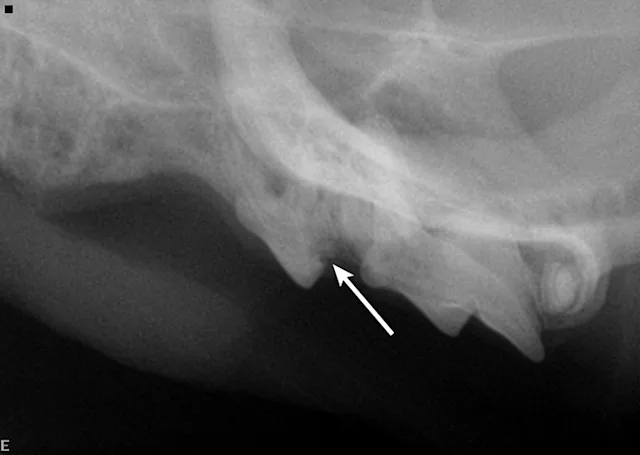

The patient periodically pawed at her face and shook her head. Oral examination revealed unhealed extraction sites with visible protrusion of tooth fragments through the gingiva (Figure 1). The areas were inflamed, and purulent exudate was present in the open alveolus of the right mandibular canine tooth (Figure 2; see Tooth Numbering).

A complete oral examination and full-mouth dental radiographs were performed with the patient anesthetized. The detailed oral examination confirmed unhealed extraction sites with sharp crown fragments protruding from the alveoli into the oral cavity. In addition, an advanced TR lesion was noted affecting the left maxillary third premolar tooth (Figure 3). Dental radiographs confirmed advanced type 2 resorption affecting all involved teeth, as well as oral extension of the remaining tooth structure (Figure 4).

Dental radiographs are crucial in establishing proper diagnosis and treatment. Teeth with type 1 TR have normal root density in some areas, as well as a well-defined periodontal space. There is generally a clearly defined root canal in the intact part of the tooth. This type may involve significant resorption of the tooth and/or root(s) that is not replaced by bone. These teeth must be completely extracted.

Teeth with type 2 TR have undergone significant replacement resorption. In these cases, the lost root structure is replaced by bone. Therefore, teeth with type 2 TR have a different radiographic density as compared with normal teeth. Radiographic findings typically include areas with no discernible periodontal ligament space (ie, dentoalveolar ankylosis) or root canal. In advanced lesions, there is little to no discernible root structure (ie, ghost roots).